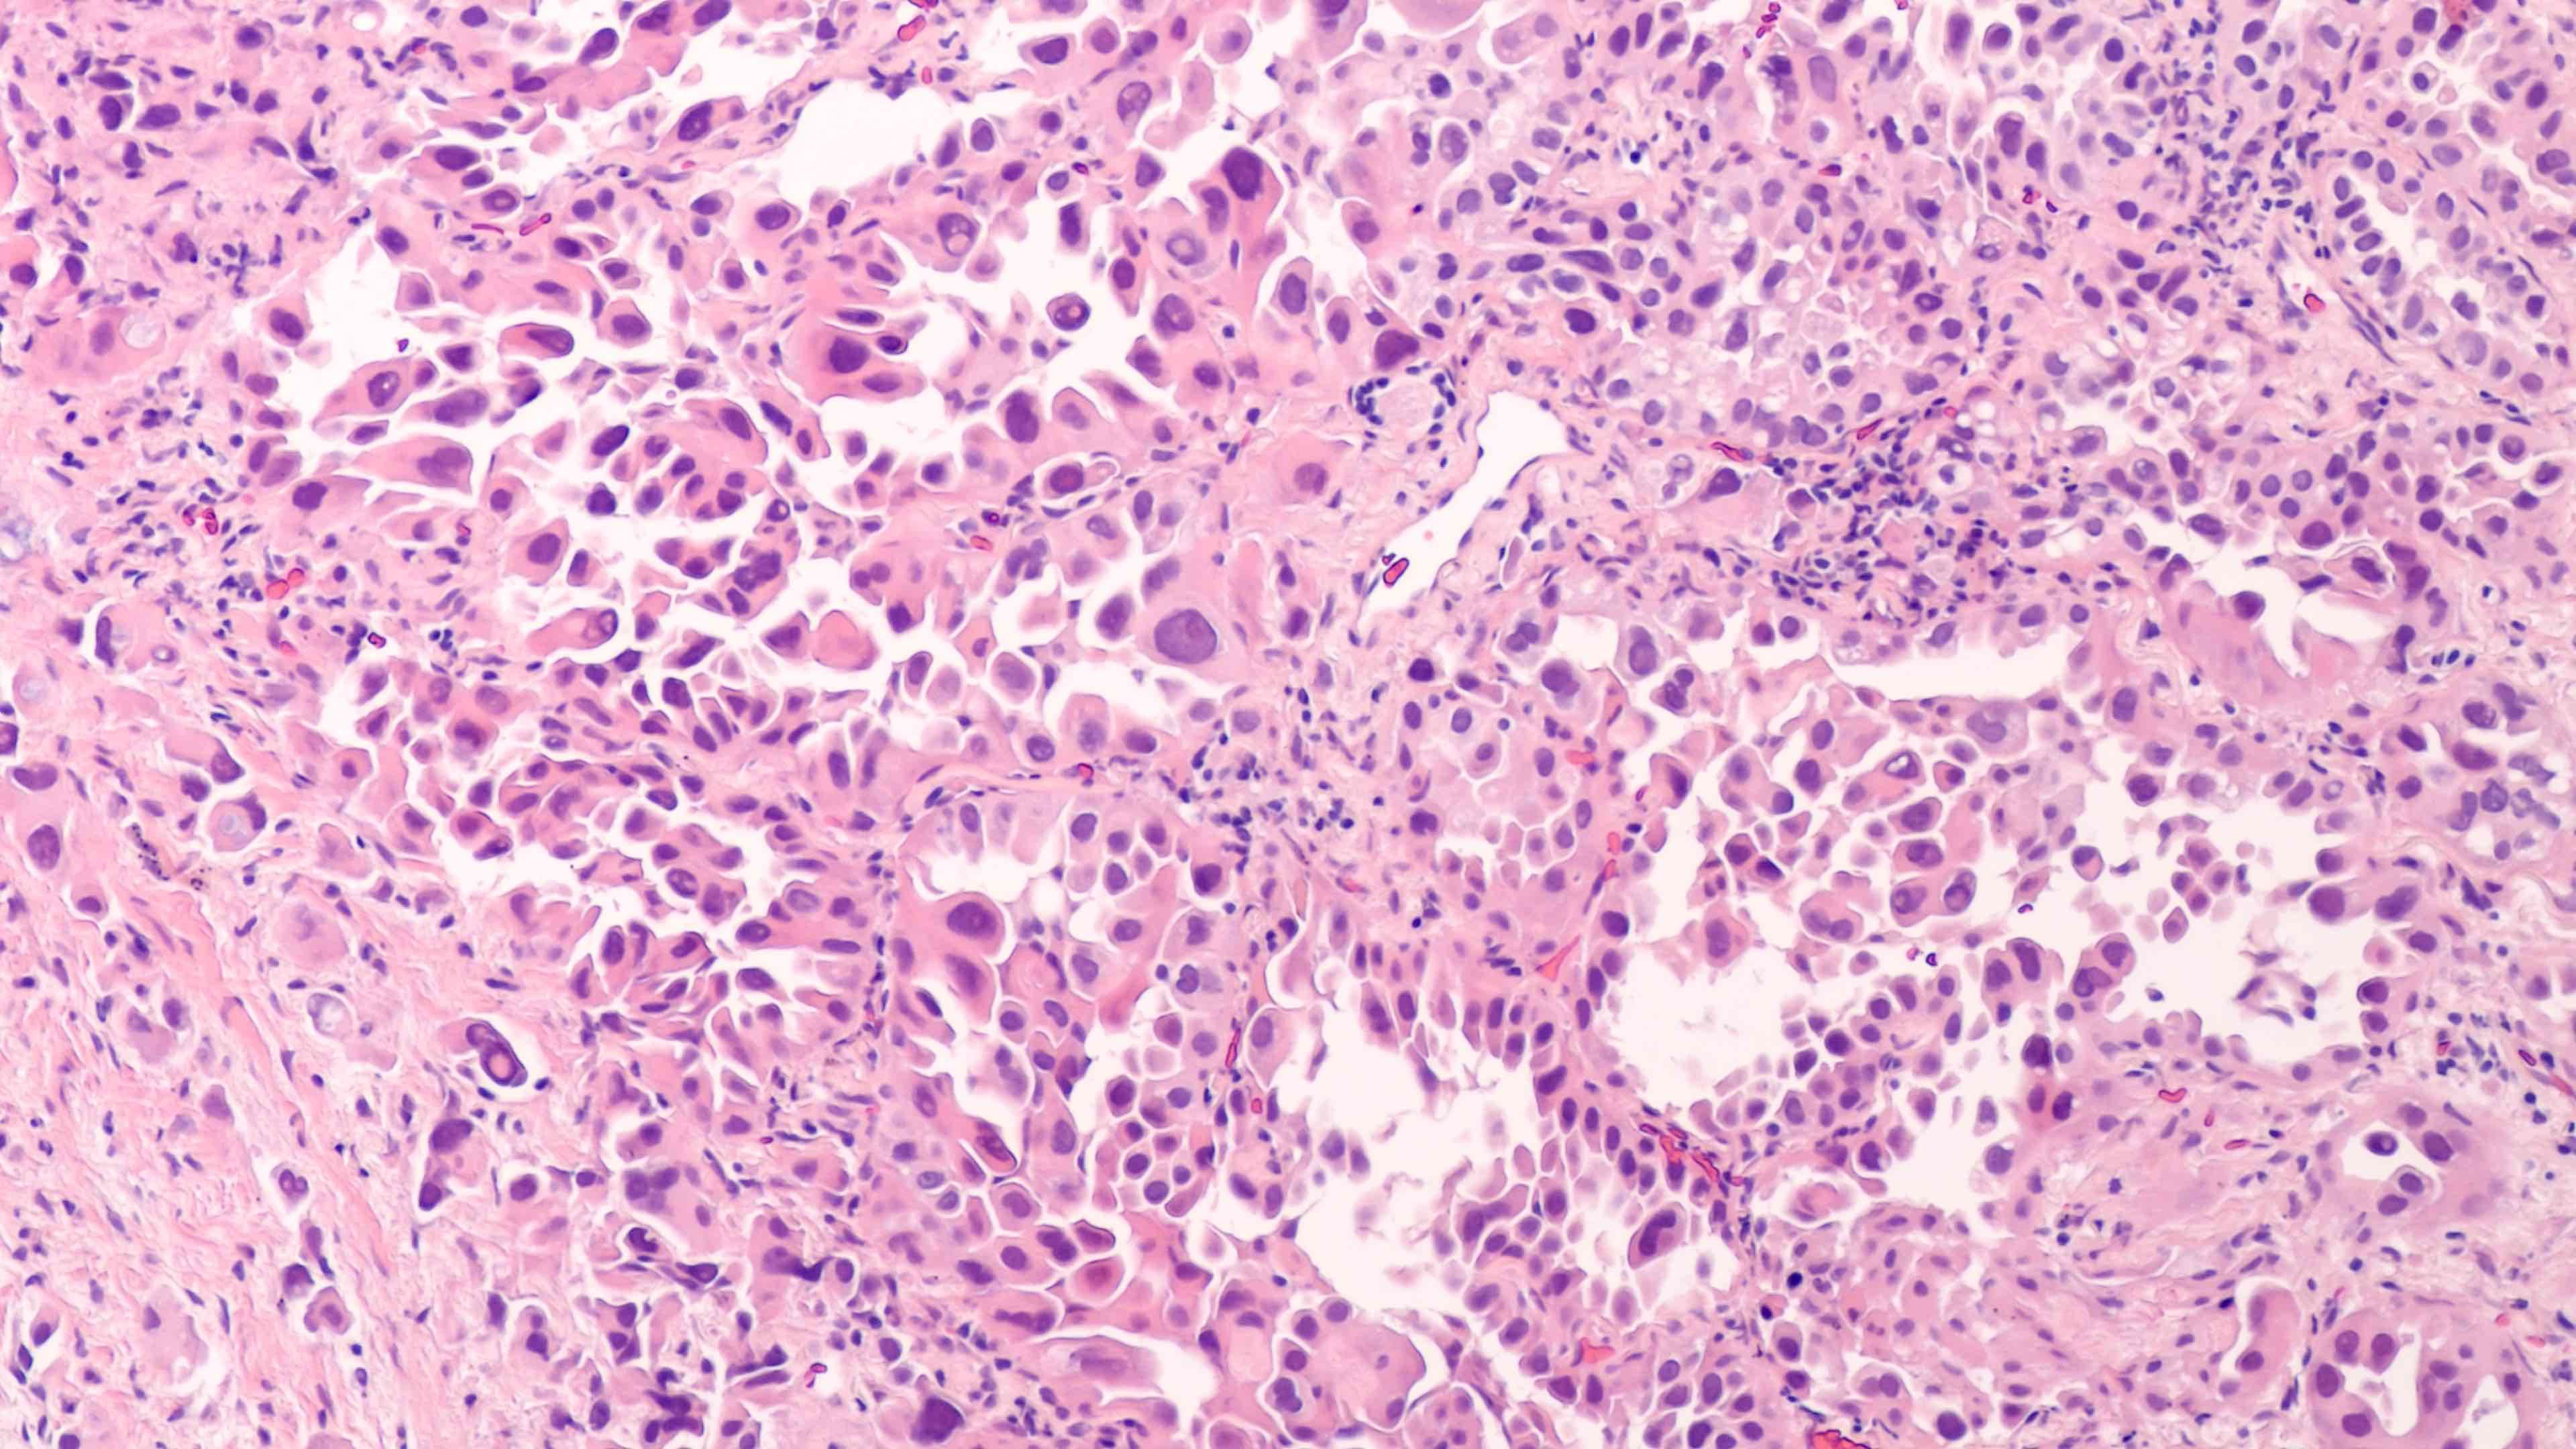

Small Cell Lung Cancer